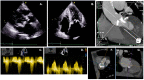

Aortic stenosis (AS) can often coexist with other valvular diseases or be combined with aortic regurgitation (AR), leading to unique pathophysiological conditions. The combination of affected valves can vary widely, resulting in a lack of standardized diagnostic or therapeutic approaches. Echocardiography is crucial in assessing patients with valvular heart disease (VHD), but careful consideration of the hemodynamic interactions between combined valvular defects is necessary. This is important as it may affect the reliability of commonly used echocardiographic parameters, making the diagnosis challenging. Therefore, a multimodality imaging approach, including computed tomography or cardiac magnetic resonance, is often not just beneficial but crucial. It represents the future of diagnostics in this intricate field due to its unprecedented capacity to quantify and comprehend valvular pathology. The absence of definitive data and guidelines for the therapeutic management of AS in the context of multiple valve lesions makes this condition particularly challenging. As a result, an individualized, case-by-case approach is necessary, guided primarily by the recommendations for the predominant valve lesion. This review aims to summarize the pathophysiology of AS in the context of multiple and mixed valve disease, with a focus on the hemodynamic implications, diagnostic challenges, and therapeutic options.